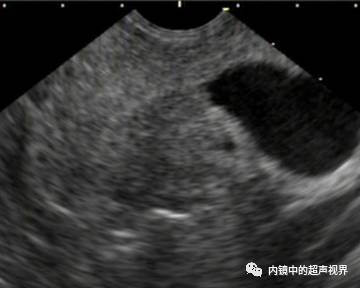

我现在使用的超声内镜DR可调节范围为30-90。以下三张图片显示的是同一个胰头肿物,肿物回声与胰腺回声非常接近,DR分别为90、70、40,其它参数相同,您更喜欢哪一张。

再来一纵隔肿物的图片,是DR30和80的对比,很明显。

再来一张间质瘤的图片,也是DR30和80的对比。

有没人觉得,这个间质瘤的图片跟前面两个病灶不太一样,似乎感觉高DR模式看起来更舒服,那是因为,间质瘤为低回声,它周围的软组织为高回声,本身就能形成良好的对比,无需降低DR,而高DR模式更显细腻。